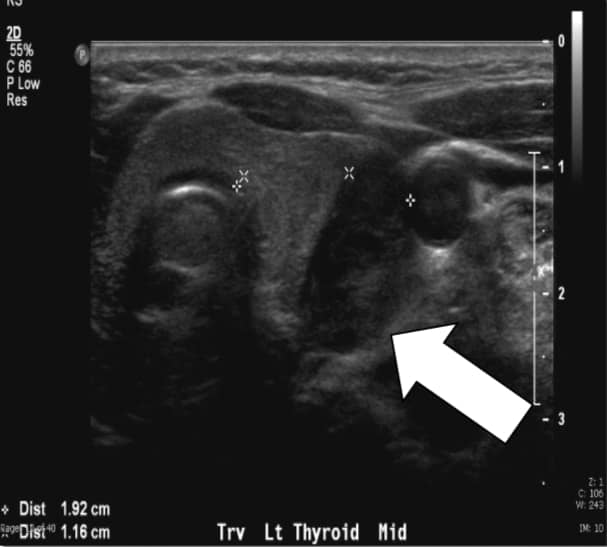

The biochemical evaluation demonstrates a total serum calcium of 10.7 mg/dl (reference range 8.8–10.2 mg/dl), elevated PTH levels of 76–81 pg/ml (reference range 10–65 pg/ml), and hypercalciuria with a 24h urine calcium of 438 mg/24h. Preoperative imaging with both ultrasound and sestamibi with single-photon emission computed tomography (SPECT) suggested a left lower parathyroid lesion.

Fig. 1a, Sestamibi with SPECT of this article's patient. Arrow indicates the parathyroid adenoma in the left lower position.We perform ultrasound routinely because it is effective, noninvasive, and inexpensive. The limitations include both operator dependency and inability to image mediastinal adenomas because it is limited to the neck. The normal parathyroid gland is generally too small to be visualized sonographically, whereas the parathyroid enlargement seen in pHPT is often identified as a homogeneously hypoechoic extrathyroidal ovoid mass. Parathyroid adenomas are typically vascular, and an arterial branch can often be followed to the superior or inferior pole of the lesion. By itself, ultrasound has approximately a 50–75% true-positive rate with generally better rates for larger glands.2